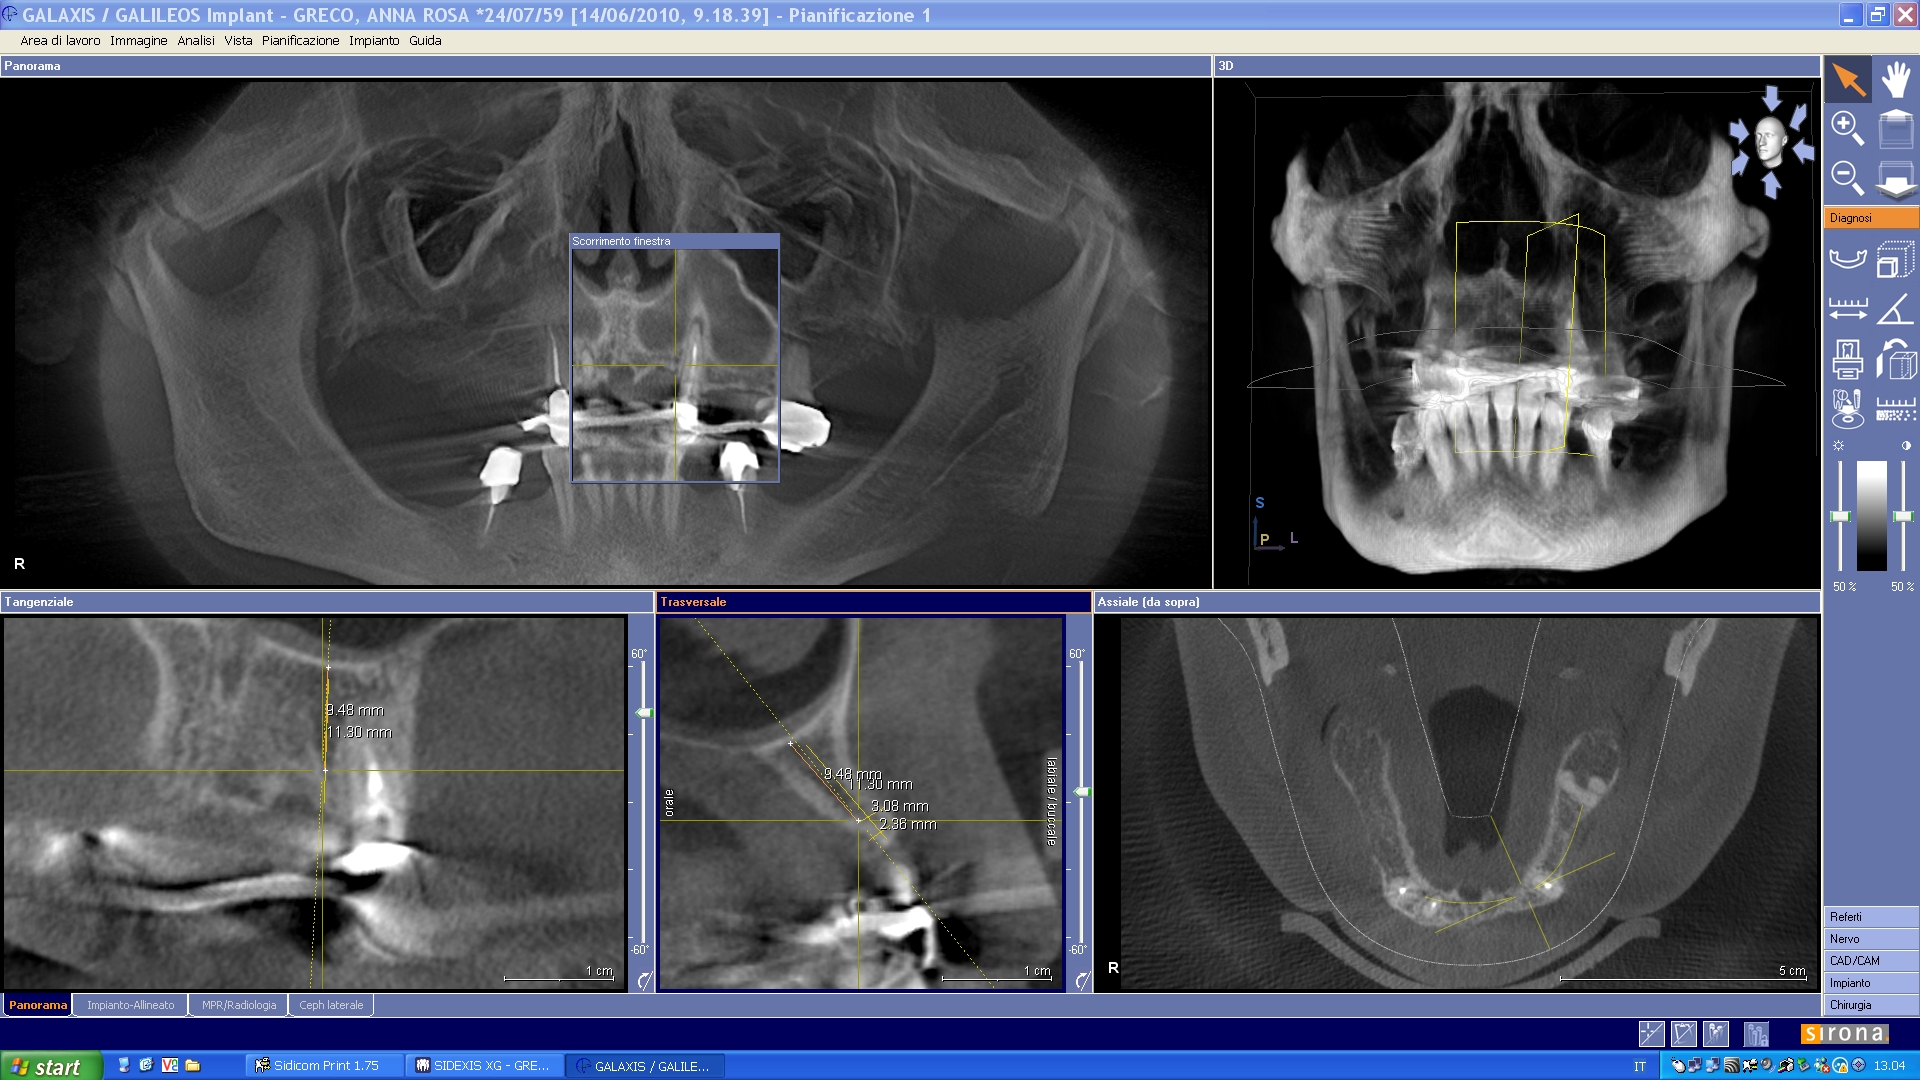

(Foto 9) Alla Tc Cone Beam 3d si evidenzia in sede 1.1-2.1 e 2.2 atrofia ossea (classe IV di Cawood e Howell) con morfologia a “lama di coltello”, altezza ossea pari a mm 9,48, spessore osseo di circa mm.3Ø e densità ossea secondo Misch D4.

Densità ossea valutata alla Tc secondo Misch

D1: >1.250 uH ; D2: 850-1250 uH; D3: 350-850 uH; D4: 150-350 uH; D5: <150 uH

(Foto 10 sezione ossea della cresta atrofica a lama di coltello in zona 2.2)

(Foto 11-12 Sezione ossea del 2.4-2.5 ) (Foto 13-14 Sezione ossea del 1.4-1.6)